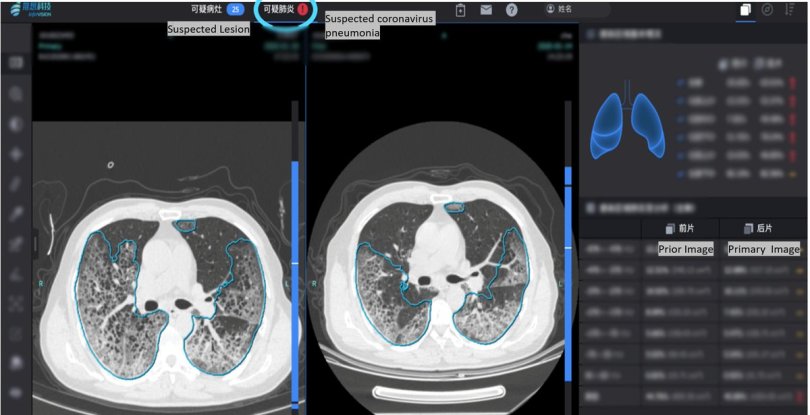

Zhongnan Hospital of Wuhan University was the first to use AI to fight the disease. To quickly diagnose patients reporting the symptoms of Covid-19, the hospital uses software developed by the Infervision startup. The system is based on artificial intelligence and analyzes lung X-rays to search for changes typical for patients infected with the virus. A few dozen Chinese hospitals have already implemented the system, which is an immense help to health facilities besieged by thousands of patients. In the case of the coronavirus, a quick diagnosis is critical, and this is where artificial intelligence comes in. The system improves itself by examining hundreds of thousands of medical scans of both healthy and sick patients. In this way, it can recognize typical early changes in the lungs, even if it is still an early stage of the disease. A similar AI-based system is helping 280 hospitals worldwide detect cancers from images.